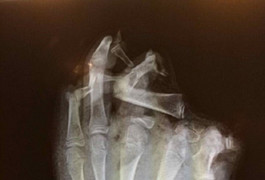

Một bệnh nhân nữa là Đ.T. H. (49 tuổi, trú quận Hải Châu, Đà Nẵng). Ông H. được chuyển đến cấp cứu vì bị dập nát bàn tay do pháo nổ. Theo lời kể của bệnh nhân, khi nhìn thấy các con đốt pháo sáng, ném vào nhau, bệnh nhân lao tới chụp pháo và bị nổ, dập tay phải. Hiện bệnh nhân được chuyển vào bệnh viện Chợ Rẫy để tiếp tục điều trị.

Trường hợp khác là nam bệnh nhân 19 tuổi, trú huyện Tiên Phước, tỉnh Quảng Nam đã tự chế tạo pháo từ phân bón, lưu huỳnh và than. Bệnh nhân cầm pháo trên tay rồi đốt, pháo nổ làm dập nát bàn tay trái, đa vết thương thành ngực trái, đùi trái và chân phải. Không chỉ vậy, những người xung quanh đứng xem cũng bị xây xước.